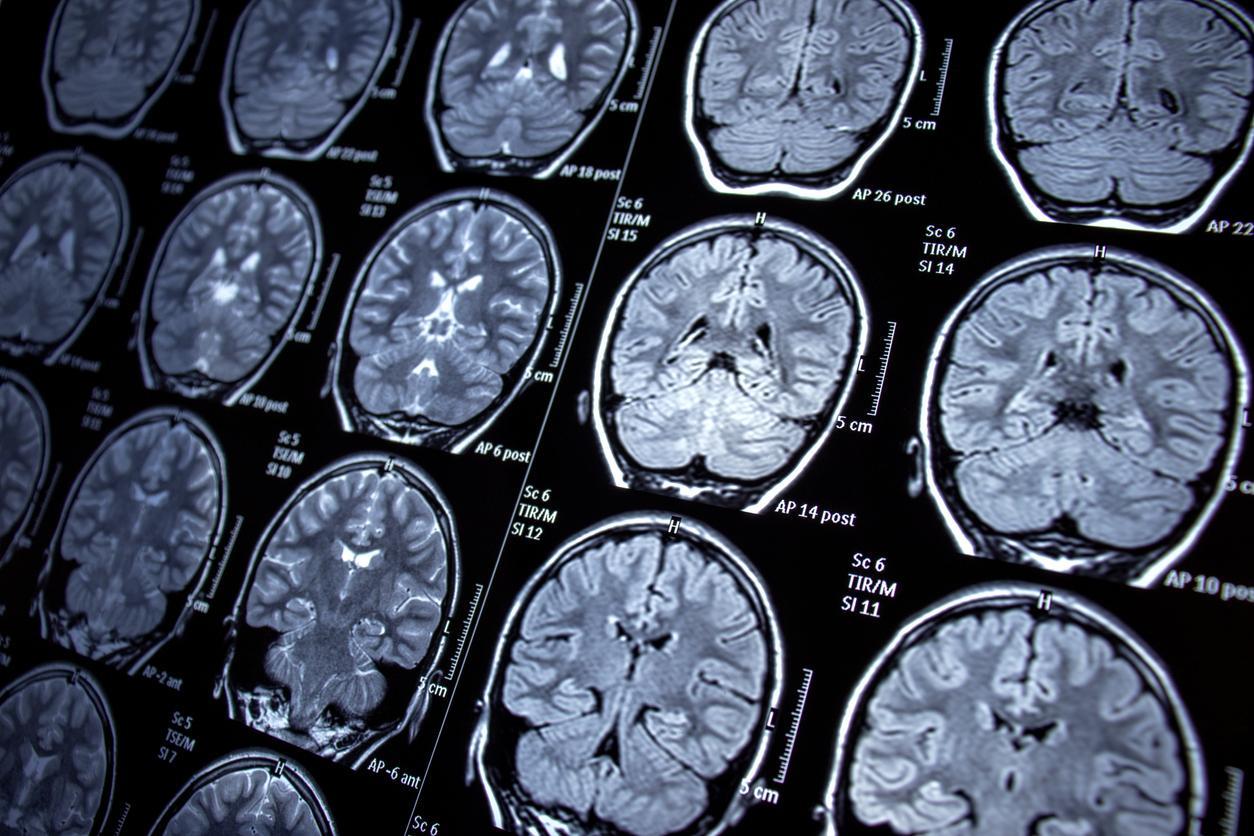

Chez une personne en bonne santé, les neurones libèrent cette protéine dans le liquide céphalorachidien, avant qu’elle ne soit ensuite éliminée dans le sang. En revanche, chez les personnes atteintes de la maladie d’Alzheimer, la structure de Tau se modifie. D'après l'Inserm, elle ne remplit alors plus correctement sa fonction à l’intérieur des neurones et s’accumule sous une forme pathologique dans le cerveau. Cette accumulation perturbe progressivement le fonctionnement cérébral et entraîne la dégénérescence puis la mort des neurones, responsables du déclin cognitif caractéristique de la maladie.

L'étude montre, à la fois chez l’animal et chez l’humain, que les tanycytes participent au transport de la protéine Tau du liquide céphalorachidien vers le sang. Il y est également révélé que la structure de ces cellules est altérée dans le cerveau de patients décédés des suites de la maladie.